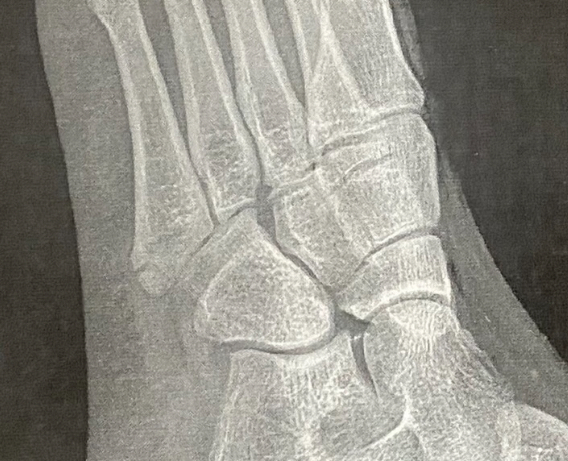

آره، اگه شکستگی ساده باشه و جابه‌جایی نداشته باشه، با اتل و بی‌حرکتی جوش می‌خوره. ولی اگه جابه‌جایی داشته باشه، ممکنه بخواد پزشک مداخله کنه.

جابه جایی نداشته با اینکه ۱۴ روز روش راه رفتم بعد که عکس گرفتم هیچ جابه جایی نداشت فقط نگران اینم که با اتل جوش میخوره یا نه🥲🥲🥲